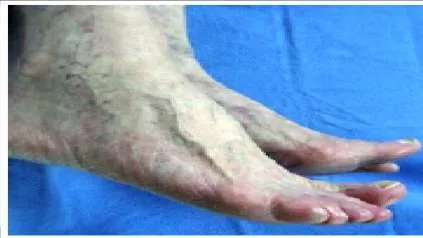

Question 33:

The patient presented (Slide 1 and Slide 2) has a hereditary sensory motor neuropathy. Based upon the photographs, a surgeon should be able to determine the pattern of muscle weakness. Weakness in which muscle is most likely the cause of this deformity:

Correct Answer: Peroneus brevis

Explanation:

Although the anterior tibial muscle is weak, the cavus is the predominant deformity of this condition, caused by weakness of the peroneus brevis. The peroneus longus is functioning and is responsible for the plantarflexion of the first metatarsal.

Question 34:

You are planning a tendon transfer to help correct deformity in a patient with hereditary sensory motor neuropathy. Which of the following muscles will be used for the transfer based upon the clinical appearance of the foot (Slide 1 and Slide 2):

Correct Answer: Posterior tibial

The posterior tibial tendon transfer is a commonly performed surgery for correction of cavus foot deformity associated with weakness of the anterior tibial muscle and varying degrees of drop foot deformity. The removal of the force of the posterior tibial tendon adds to the correction of the deformity of the foot by balancing the absent peroneus brevis. Although the extensor hallucis longus can be used as a tendon transfer, it will not be the primary muscle used or sufficient to correct deformity.